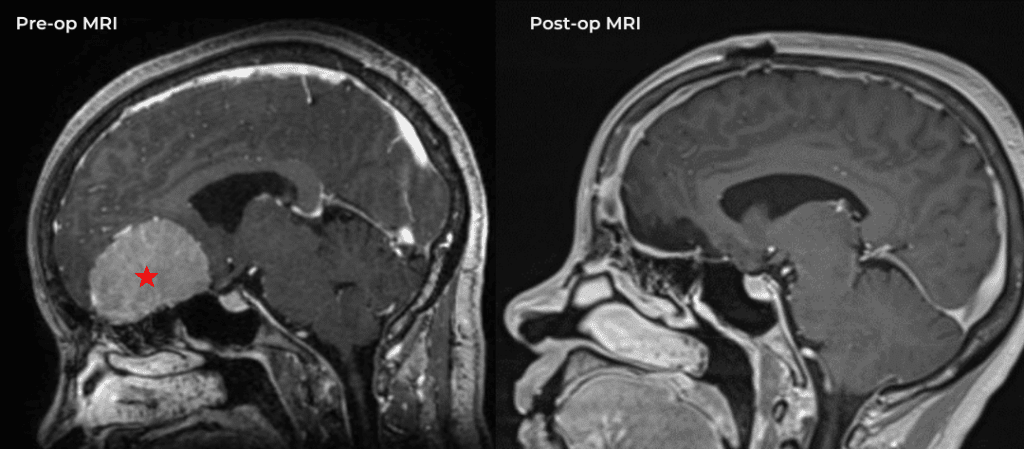

Brain:

Pineal Region Meningioma

Author: Michael Brisman M.D., F.A.C.S., Read More!